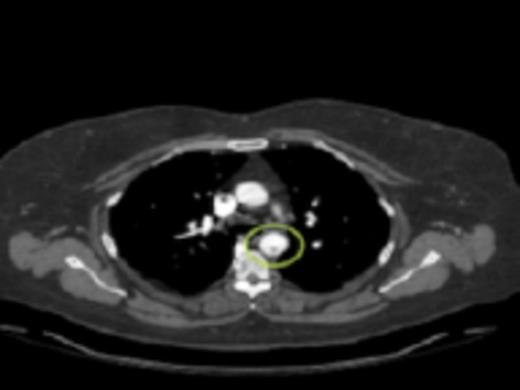

A cross sectional CT-angiogram showing the mobile aortic plaque in the descending thoracic aorta. This image is taken prior to intervention

Initial workup included a transesophageal echocardiogram (TEE) which showed a 0.8cm × 0.9cm highly mobile plaque just distal to the take-off of the left subclavian artery. CT angiography (CTA) was then performed to further delineate the anatomy and to evaluate for the possibility of endovascular stent graft placement. CTA showed a thoracic aortic intraluminal filling defect which represented a small area of clot within an atherosclerotic plaque. The CTA also demonstrated an area of decreased attenuation on the upper anterior portion of the spleen consistent with an older splenic infarct.